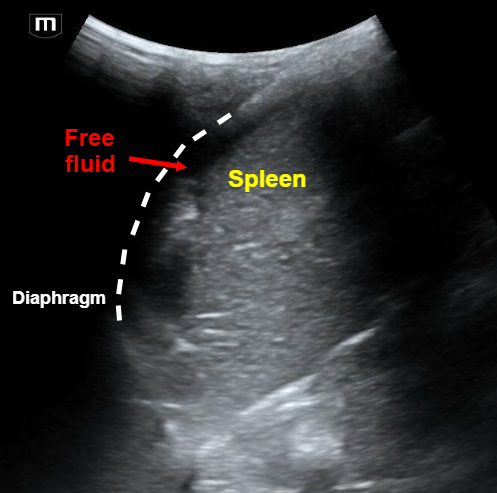

The team did a FAST and here are some labeled images from their respective clips:

Clip 1 is a LUQ that shows free fluid below the diaphragm on top of the spleen.

• LUQ is more posterior + superior than RUQ – Look at splenorenal, subdiaphragmatic, inferior pole